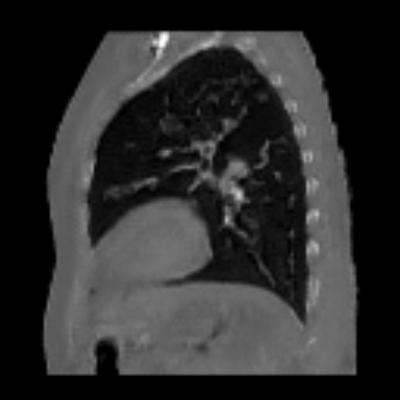

| Axial | Coronal | Sagittal | |

| X2CTGAN | ![]() |

![]() |

|

| DX2CT | ![]() |

| Ground-truth | ![]() |

Figure 3 and Table I(a) using biplanar X-rays show that proposed DX2CT can outperform three existing SOTA methods. Figure 3 shows that DX2CT can provide more accurate overall shapes and details compared to the existing methods. The quality of reconstructed CT slices in the axial plane is less satisfactory than those in the other planes. The reason is that the axial plane is perpendicular to the planes of biplanar X-rays so there exists less spatial (i.e., depth) information in the axial plane. Without using the perceptual loss [33], proposed DX2CT gave comparable LPIPS results with PerX2CTs using [33] in training. Compare their LPIPS results in Table I(a).